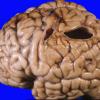

Hypoxia-Ischemia, fetal-neonatal

Porencephaly (2)